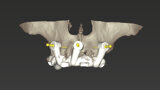

Compromised maxillary dentition treated with Straumann Pro Arch and a digital workflow